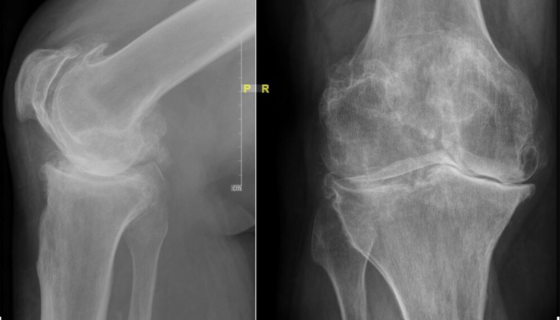

Vor einer Operation führen wir eine gründliche Untersuchung und spezielle Röntgenaufnahmen durch. Gemeinsam mit Ihnen besprechen wir, welche Art von Prothese für Ihr Knie am besten geeignet ist. Anschließend planen wir die Operation sorgfältig, einschließlich der genauen Größe und Form der Prothese, damit diese optimal passt und Ihnen im Alltag wieder mehr Beweglichkeit und Lebensqualität ermöglicht.

Vor der Operation erfolgt eine orthopädische Untersuchung und ausführliche Beratung zu konservativen und operativen Therapiemöglichkeiten, sowie Erfolgsaussichten und Risiken. Wenn eine Operation geplant ist, wird diese verständlich erklärt und alle Fragen beantwortet. Es schließen sich moderne Röntgendiagnostik, laborchemische Kontrollen sowie ein ausführliches Gespräch mit dem Anästhesisten an.